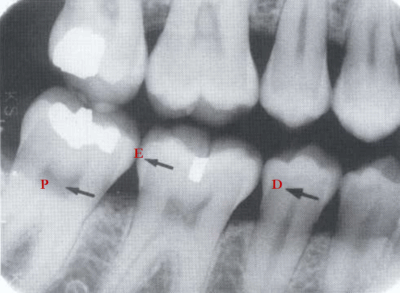

79. What is E showing?

Enamel Teeth are made up of 4 basic anatomic structures: Enamel, dentin, cementum, and pulp. Hardest substance in body = most mineralized (95% calcified) → highest radiographic density Covers crown of tooth; contacts dentin at dentinoenamel junction (DEJ) Contacts cementum at cementoenamel junction (CEJ)

80. What is D showing?

Dentin • Makes up majority of tooth (70-75% calcified) → less opaque than enamel and more comparable to bone

81. What is P showing?

Pulp Contains nerves and vessels that enter and emerge through apical foramen. Most radiolucent portion of tooth. Crown portion called pulp chamber with pointy pulp horns; root portion called pulp canal. Lateral canals: may occur as branches of a normal root canal and usually found at the apical third of the root. With aging occurs a gradual deposition of secondary dentin. This process may eventually lead to pulp obliteration.